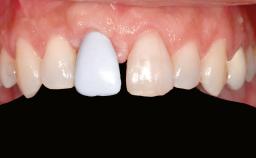

Shell Technique for Horizontal and Vertical Maxillary Bone Augmentation in a Partially Edentulous Patient with Aggressive Periodontal Disease

Patient's Esthetic Expectations Low Medium High

Lip Line No exposure of papillae Exposure of papillae Full exposure of mucosa margin

Periodontal Phenotype Low-scalloped, thick Medium-scalloped, medium-thick High-scalloped, thin